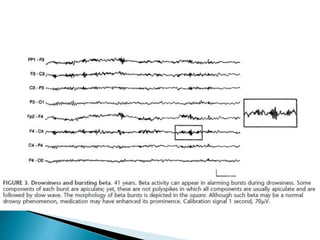

 High doses of several types of medications may

elicit spikes or poly spikes that usually appear

bisynchronously in bursts, either spontaneously

or as a photoparoxysmal response

 Clozapine, Lithium, Phenothiazines, selective

serotonin reuptake inhibitors, and tricyclic

antidepressants.

 Acute withdrawal of alcohol or barbiturates may

also elicit bursts of spikes and polyspikes,

particularly as a photoparoxysmal response

(G. Bauer and R. Bauer, 2005; Van Cott and Brenner, 2003)

 High dosesof several types of medications may elicit spikes or poly spikes that usually appear bisynchronously in bursts, either spontaneously or as a photoparoxysmal response  Clozapine, Lithium, Phenothiazines, selective serotonin reuptake inhibitors, and tricyclic antidepressants.  Acute withdrawal of alcohol or barbiturates may also elicit bursts of spikes and polyspikes, particularly as a photoparoxysmal response (G. Bauer and R. Bauer, 2005; Van Cott and Brenner, 2003)